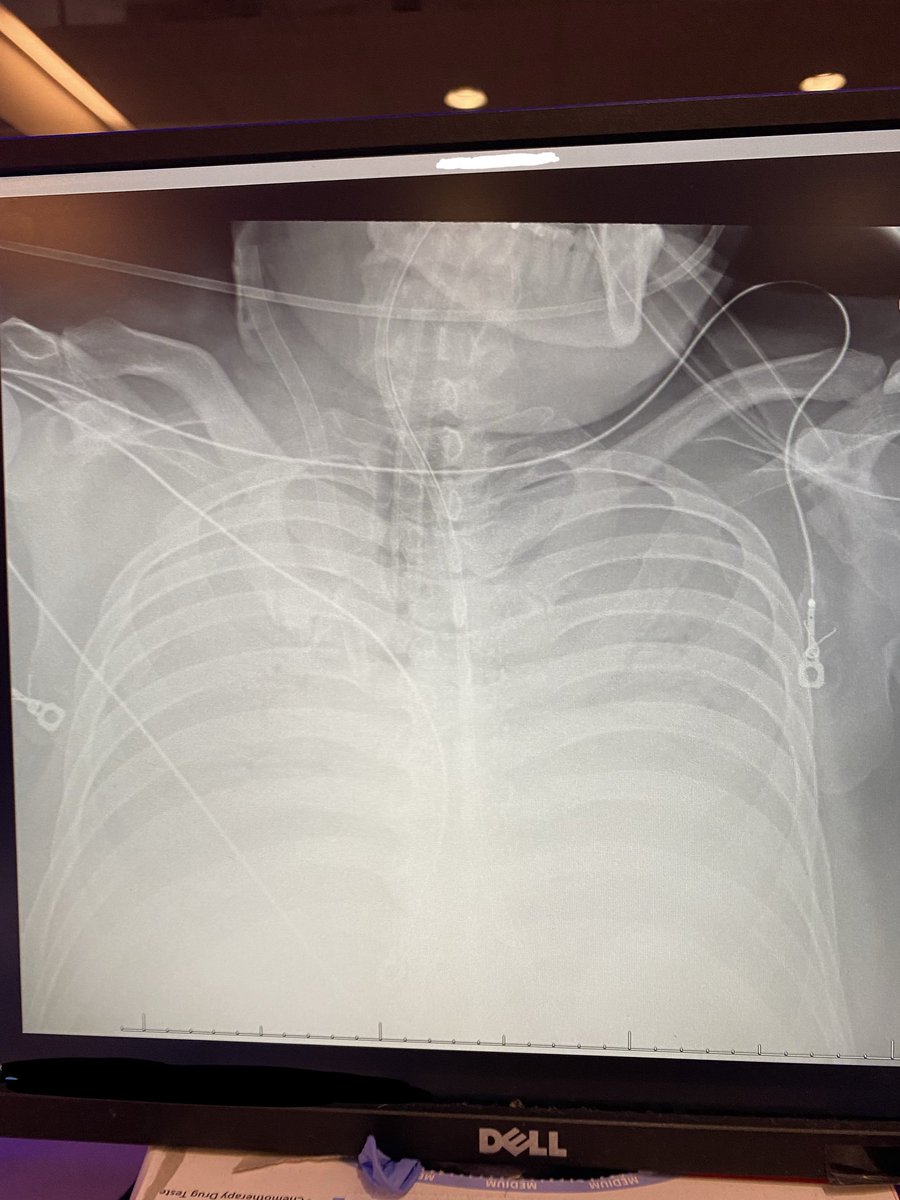

Your thoughts